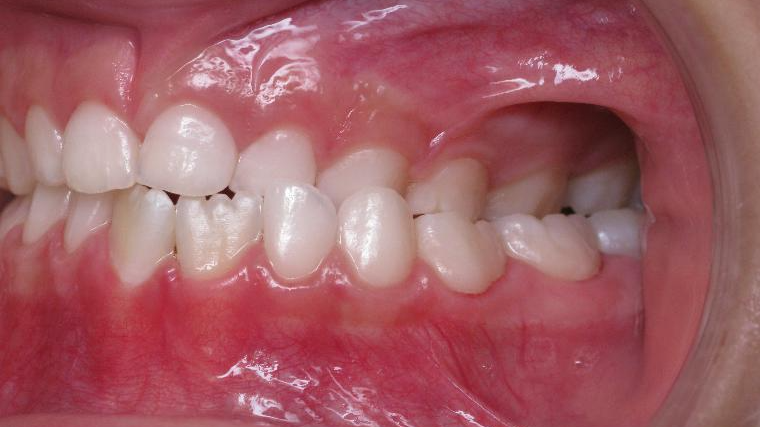

inversion des dents posterieur cote gauche

bilan début et fin de traitement